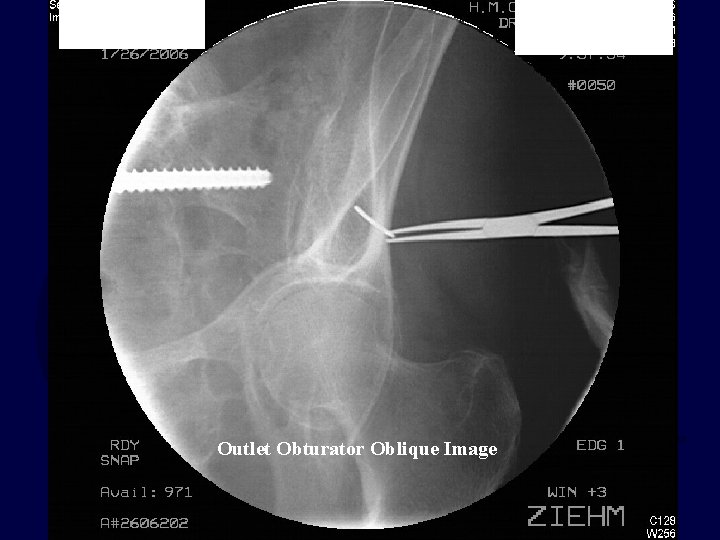

• Outlet Obturator Oblique Image

5 degrees too much obturator 5 degrees too little obturator 5 degrees too much outlet 5 degrees too little outlet

Outlet Obturator Oblique Image